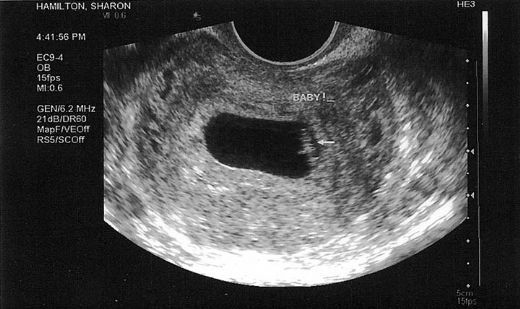

7 Haftalık Gebelikte (Hamilelikte) Kanama Nedenleri?

3 Aylık Gebelikte (Hamilelikte) Kanama Nedenleri?